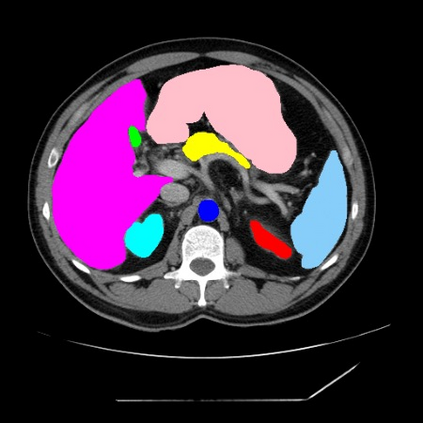

Integrating high-level semantically correlated contents and low-level anatomical features is of central importance in medical image segmentation. Towards this end, recent deep learning-based medical segmentation methods have shown great promise in better modeling such information. However, convolution operators for medical segmentation typically operate on regular grids, which inherently blur the high-frequency regions, i.e., boundary regions. In this work, we propose MORSE, a generic implicit neural rendering framework designed at an anatomical level to assist learning in medical image segmentation. Our method is motivated by the fact that implicit neural representation has been shown to be more effective in fitting complex signals and solving computer graphics problems than discrete grid-based representation. The core of our approach is to formulate medical image segmentation as a rendering problem in an end-to-end manner. Specifically, we continuously align the coarse segmentation prediction with the ambiguous coordinate-based point representations and aggregate these features to adaptively refine the boundary region. To parallelly optimize multi-scale pixel-level features, we leverage the idea from Mixture-of-Expert (MoE) to design and train our MORSE with a stochastic gating mechanism. Our experiments demonstrate that MORSE can work well with different medical segmentation backbones, consistently achieving competitive performance improvements in both 2D and 3D supervised medical segmentation methods. We also theoretically analyze the superiority of MORSE.

翻译:在医学图像分割中,整合高级语义相关的内容和低级解剖特征对于模拟这些信息非常重要。近期基于深度学习的医学分割方法已经显示出很有前景,可以更好地建模这些信息。然而,医学分割的卷积运算符通常在正则化网格上运作,这在本质上模糊了高频区域,即边界区域。我们在这项工作中提出了 MORSE,这是一个设计在解剖学水平上的通用隐式神经渲染框架,用于协助医学图像分割的学习。我们的方法的动机在于隐式神经表示已经被证明比离散化网格表示更有效地拟合复杂信号和解决计算机图形问题。我们方法的核心是将医学图像分割连续地对准粗糙的分割预测和模棱两可的基于坐标的点表示,并聚合这些特征来自适应地精细化边界区域。为了并行地优化多尺度像素级特征,我们借鉴了 Mixture-of-Expert (MoE) 的思想设计和训练我们的MORSE,使用随机门控机制。我们的实验表明MORSE可以很好地与不同的医学分割后骨干结合在一起,始终在2D和3D监督医学分割方法中实现了有竞争力的性能改进。我们还从理论上分析了MORSE的优越性。